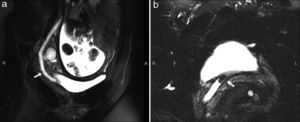

The uro-MR, especially the sequences that are highly T2-weighted allows us to detect excretory duct dilation63,64 and distinguish pregnancy physiological hydronephrosis from that secondary to lithiasis. Although lithiases can go unnoticed, when the urinary tract is dilated they are usually identified as filling defects with signal void (Fig. 5). MRIs are a good alternative to CT for pregnant women with negative or non-conclusive ultrasound result yet its safety is not proved in the first quarter, its use is arguable and it must only be indicated after the assessment of the risk-benefits ratio. On the other hand, the availability of MR machines for emergency studies is very limited.

Magnetic resonance in a 20-week pregnant patient with right renal colic. (a) Coronal reconstruction showing ureter dilation (arrow) up to the pelvis. (b) T2-weighted axial sequence showing dilated distal ureter with juxtavesical intraureteral signal void image corresponding to lithiasis (arrow).